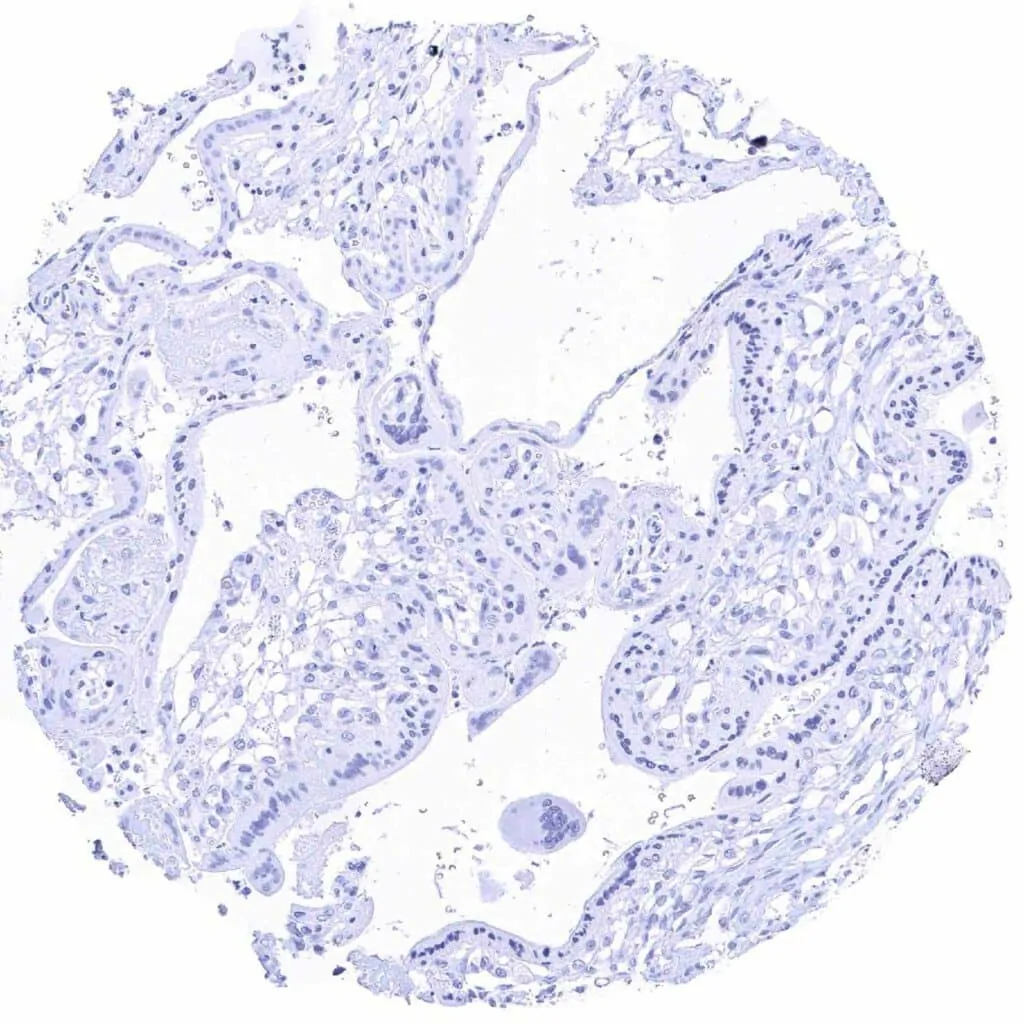

Fallopian tube, mucosa